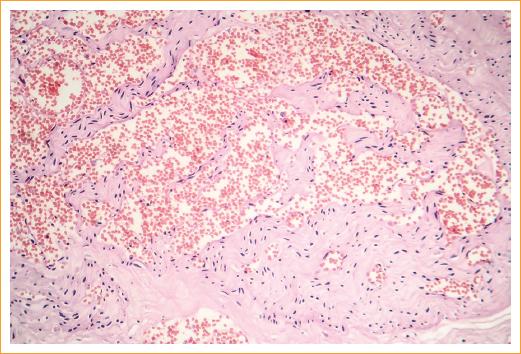

El aspecto histopatológico de este hamartoma vascular varía con su fase clínica. En la fase proliferativa temprana, el tumor consiste sobre todo en células endoteliales, y los espacios vasculares son raros, así mismo, contiene numerosos mastocitos. En los tumores más maduros se observan espacios vasculares más grandes, con menor número de células endoteliales (Fig. 3). El tumor no se encapsula y, generalmente, no tiende a infiltrar las estructuras circundantes. En la fase involutiva hay a menudo deposición del tejido fibroso y adiposo alrededor y dentro de la lesión3.